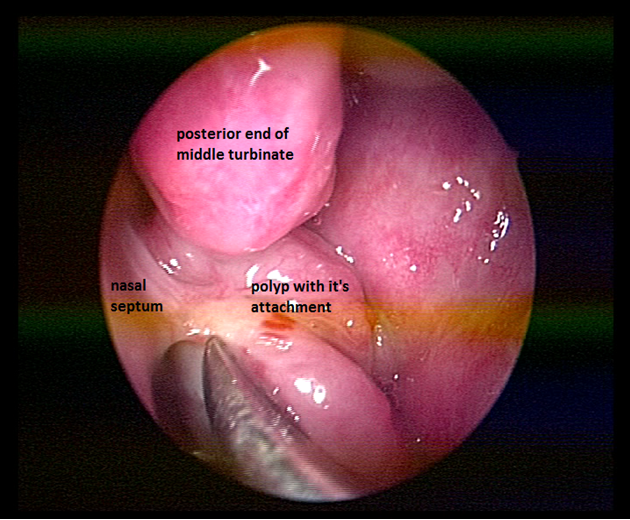

A 25year old man presented with history of progressive bilateral nasal obstruction and snoring for the past two years. There was no history of nasal discharge, post nasal drip, nasal bleeding and his wife reported difficulty in sleeping in the same room with the patient due to snoring. Anterior rhinoscopy was normal. On diagnostic nasal endoscopy a lobulated mass arising from the superior aspect of posterior septum on left side, obstructing whole of the choana was seen (Figure 1). Computed tomography revealed a soft tissue mass occupying whole of the nasopharynx abutting the nasal septum (Figure 2). Paranasal sinuses were normal. Patient was taken up for endoscopic excision and biopsy. Local anesthesia was infiltrated in the pedicle and the stalk of the polyp was resected with the small amount of normal surrounding mucosa. The base of the stalk was cauterized with bipolar cautery. No nasal packing was required and patient was discharged on the same day. Macroscopically the mass was of around 5X2X2cm with lobulated surface and multiple firm nodules were palpable over the surface (Figure 3). On cut section white strands were found, along with few cystic areas (Figure 4). Histopathology revealed a polypoidal tissue mass with marked inflammatory infiltrate containing mostly lymphocytes with lack of Stromal edema and goblet cell hyperplasia; these were suggestive of fibroinflammatory polyp. Postoperative period was uneventful. There was no recurrence in the six months follow up.

Figure 1 Endoscopic photograph on left side showing the polyp filling the posterior choana and its attachment on the superior aspect on posterior septum.